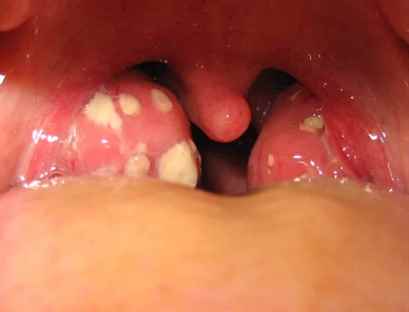

- Изменения в горле: При осмотре горла можно заметить покраснение, отек миндалин, а также наличие налета или гнойных пробок.

Явные признаки ангины

При симптомах ОРВИ нужно обратить внимание на то, сколько дней держится температура. Если у ребенка постоянно болит горло, а температура не спадает 2-3 дня, это может быть признаком ангины. Явным признаком инфекции горла в данной ситуации будет полное бездействие жаропонижающих средств. Если у ребенка ангина, они не помогут, снизить температуру смогут только антибиотики.